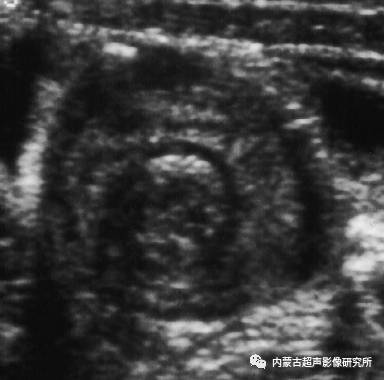

对于腹痛或腹泻的儿童,在我们日常工作中常常会发现以下超声征象:1、在上腹部通常为左上腹肠管横切可见到“同心圆”征象,纵切呈“套袖”征象(图1);2、“同心圆”直径比较小通常≤52.5px,“套袖”长度比较短通常≤87.5px;3、套叠处肠壁无明显水肿,周围无积液,近端小肠扩张不明显;4、套入肠管蠕动频繁;5、套叠包块内有时可见肠系膜套人(图2),但未见像原发性肠套叠常见的将淋巴结或阑尾套入其中的表现;6、彩色多普勒:套叠处小肠壁可见明显血流信号(图3);7、所有套叠包块在最长24 h内均自行复位,无需灌肠治疗更不需手术复位。

图1